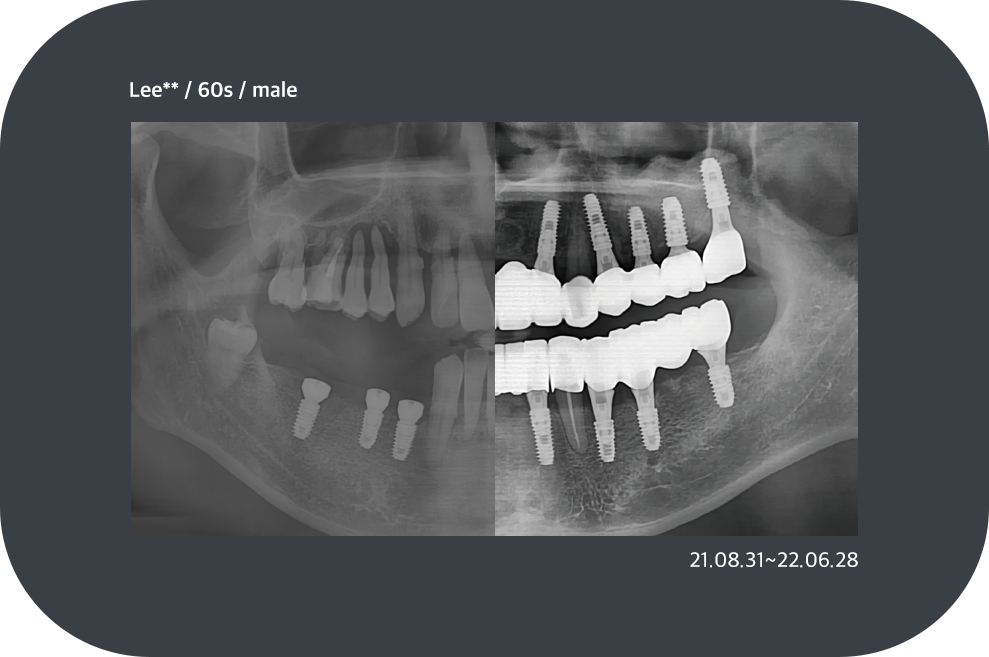

치료사례

임플란트 치료사례

*모든 증례 사진은 의료법 제23조, 제56조에 의거하여, 당사자의 동의하에 게시하였습니다.

*치료 사진은 모두 본원에서 치료한 환자분의 사진입니다.

*치료 사진은 모두 동일인의 사진이며, 동일조건에서 촬영하였습니다.

*개인의 차이에 따라 시술 및 수술 후 부작용이 발생할 수 있으며, 의료진과 충분한 상담을 받으시기 바랍니다.